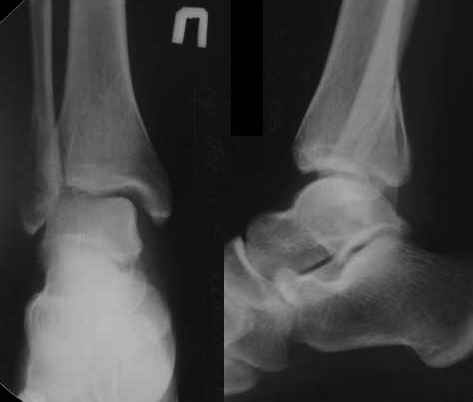

Консолид. перелом г/ стопного |

Уважаемые коллеги! Госпитализировал симпатичную девушку 22 года. Травма 15.01.06.

Лечилась в гипсовой повязке, иммобилизация 6 недель.

После снятия гипса на рентгене смещение отломков. Планирую репозицию наружной лодыжки ( фиксация треть трубчатой пластиной) и заднего края б/б кости (винт). Однако, есть вопросы: 1)доступ (планирую из одного заднего доступа, реально?), 2)остеотомия по линиям перелома или целесообразнее как-то иначе? 3)нуждается ли дельтовидная связка в хирургическом вмешательстве?

С уважением, А.Минервин.